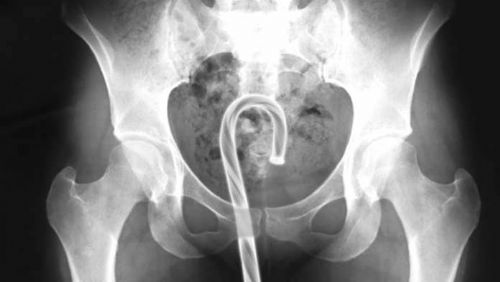

Röntgen filmlerinden "akıl almaz şeyler

Hastane koridorlarına düşenler bilir… Doktora görün, tahlilleri yaptır, röntgenleri çektir falan filan derken sayılmadan ömür gider. Gelin ki bu sefer ilginç şeyler çıkmış ki görün ağzımız açık kaldı…